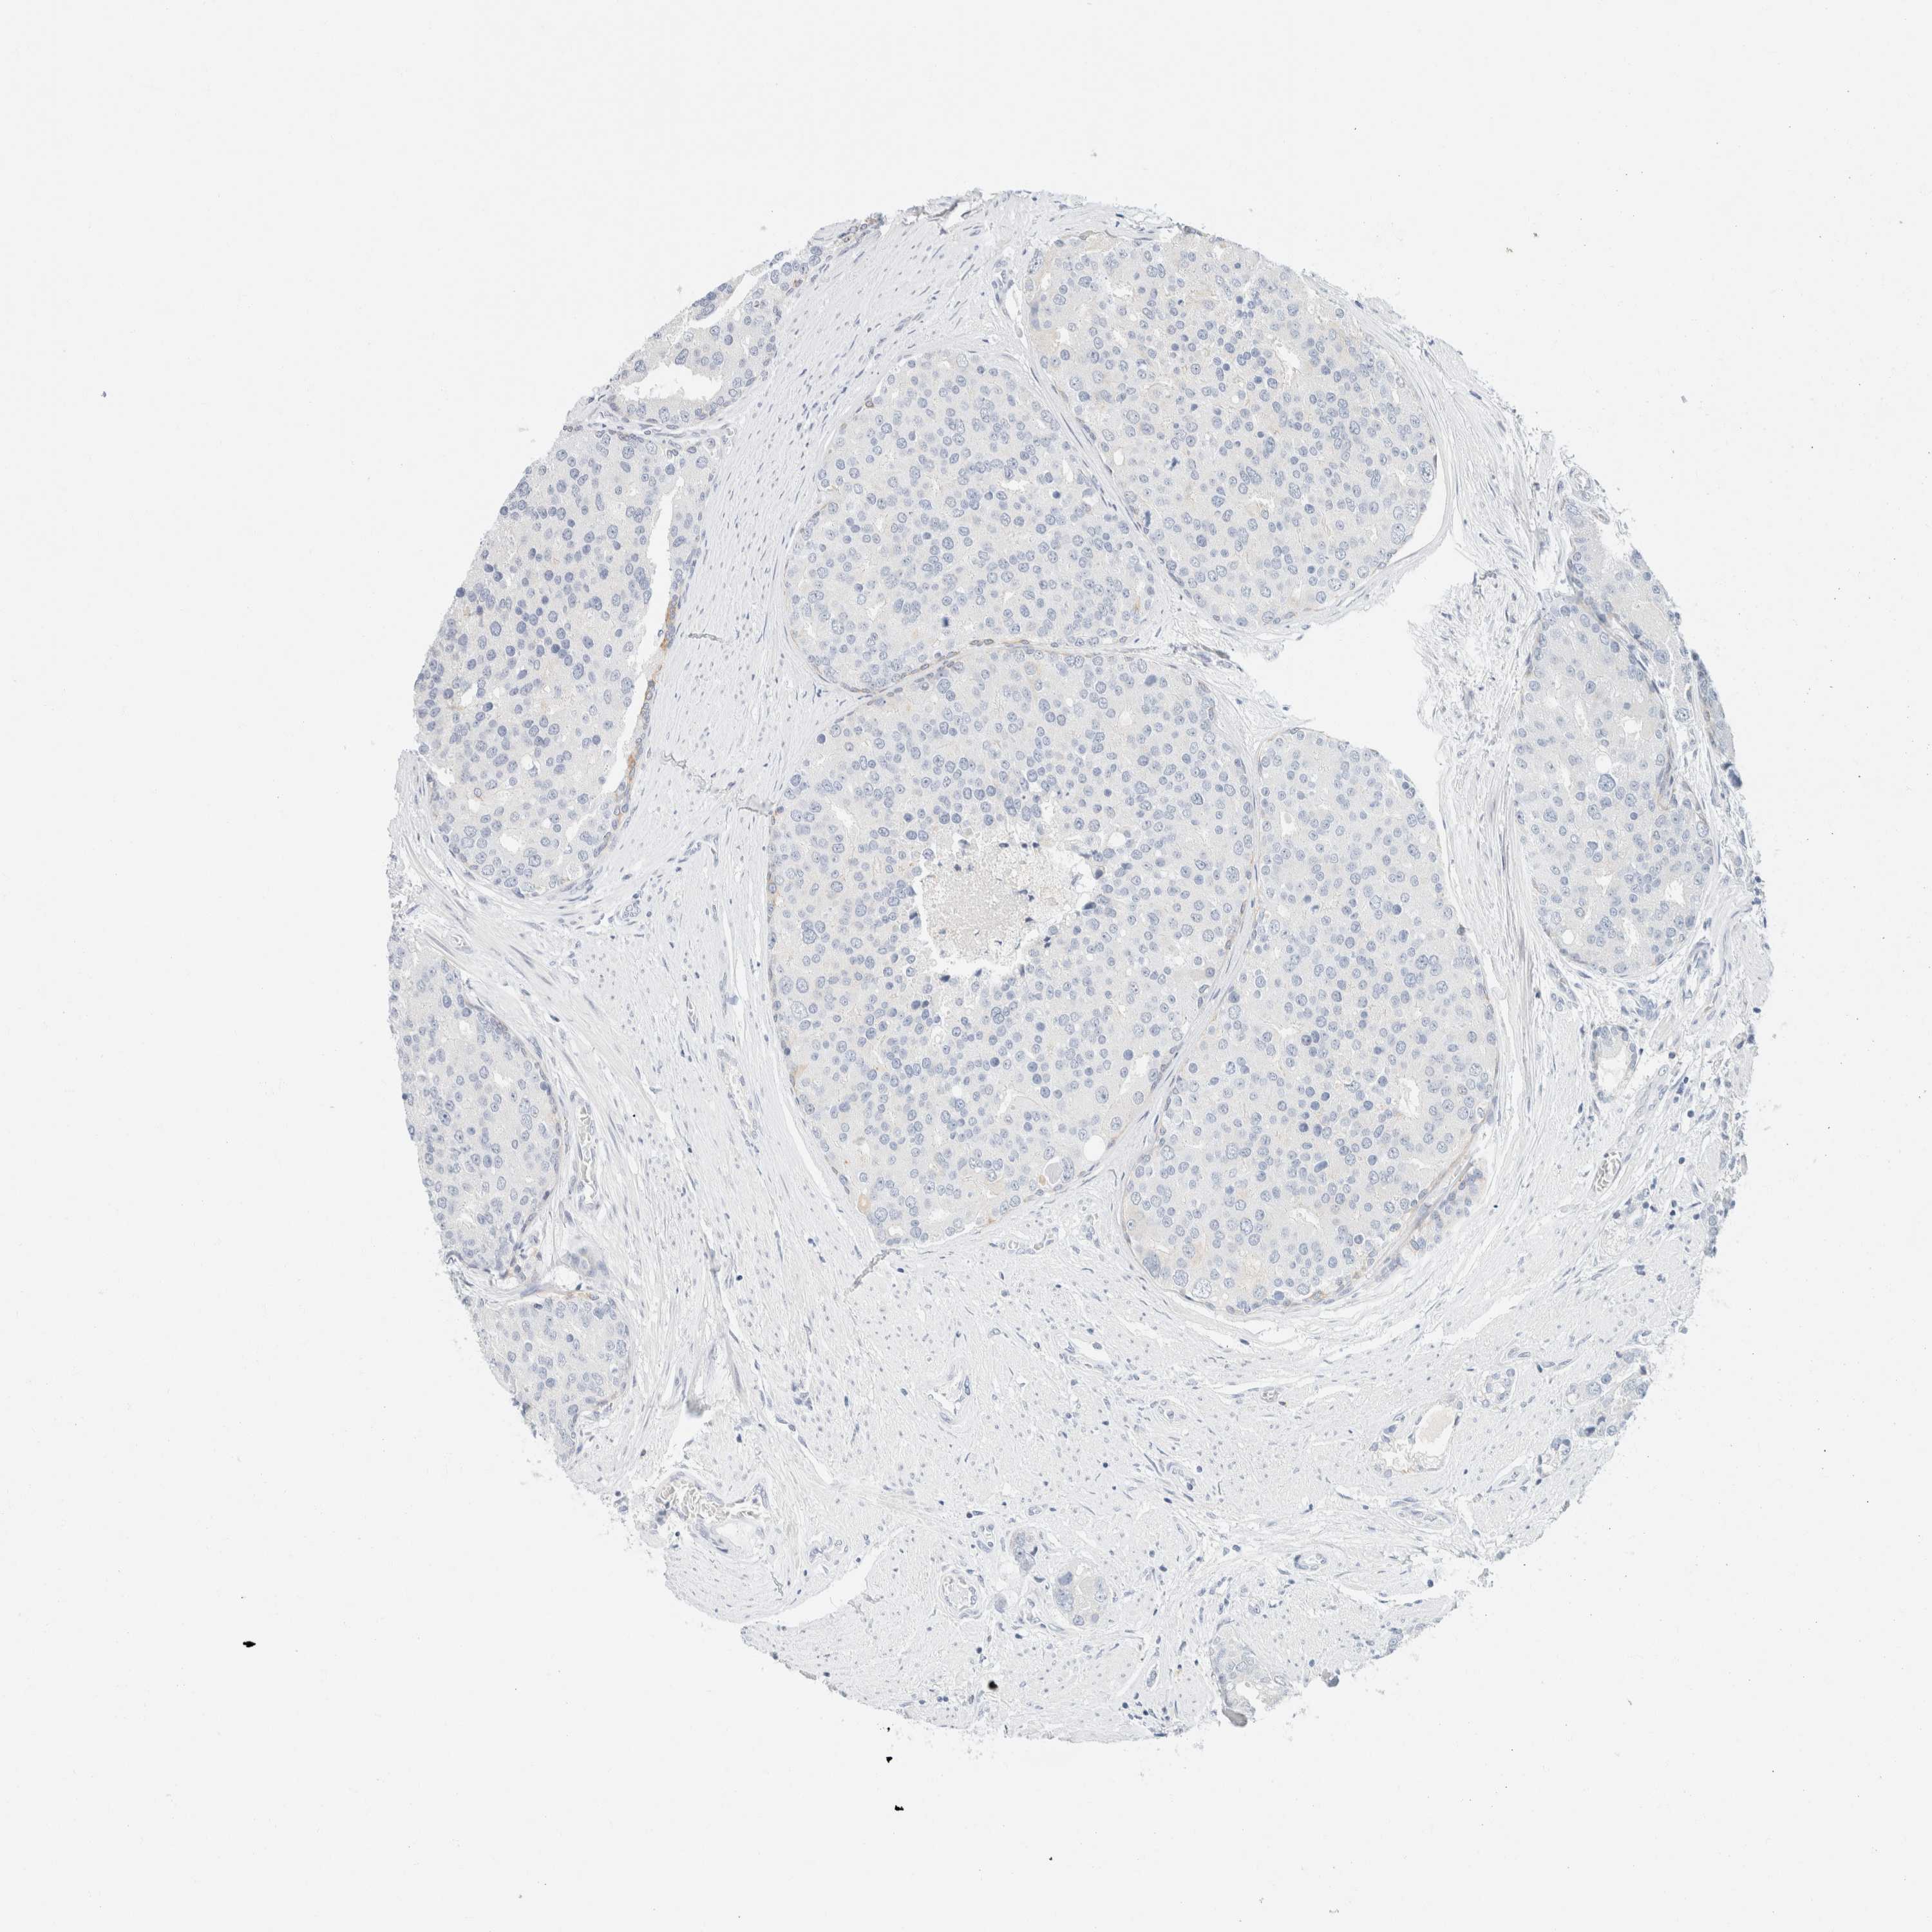

PROSTATE CANCER - Protein expressioni

A mouse-over function shows sample information and annotation data. Click on an image to view it in a full screen mode. Samples can be filtered based on level of antibody staining by selecting one or several of the following categories: high, medium, low and not detected. The assay and annotation is described here.

Note that samples used for immunohistochemistry by the Human Protein Atlas do not correspond to samples in the TCGA dataset.

Antibody stainingi

Antibody staining in the annotated cell types in the current human tissue is reported as not detected, low, medium, or high, based on conventional immunohistochemistry profiling in selected tissues. This score is based on the combination of the staining intensity and fraction of stained cells.

Each image is clickable and will lead to virtual microscopy that enables deeper exploration of all samples and also displays staining intensity scores, fraction scores and subcellular localization as well as patient and tissue information for each sample.

Antibody HPA024309

Antibody HPA024684

Antibody HPA027236

Antibody CAB000032

Adenocarcinoma, High grade

Adenocarcinoma, Low grade

Adenocarcinoma, Medium grade